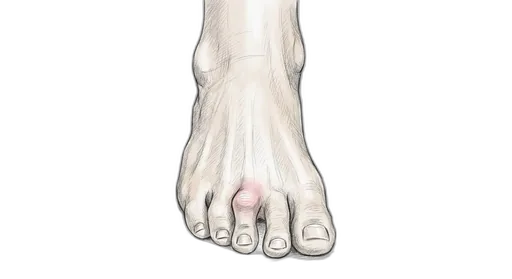

Foot & Ankle Exercise Guide

Choose your condition below to get started with exercises and stretches designed by Dr. Patish.

Pick your condition below, and you'll find your personalized exercise program — with medical illustrations, step-by-step instructions at three intensity levels, and clear guidance on when to call our office. Every protocol here is the same one Dr. Patish prescribes to patients in the clinic.

Forefoot & Toes